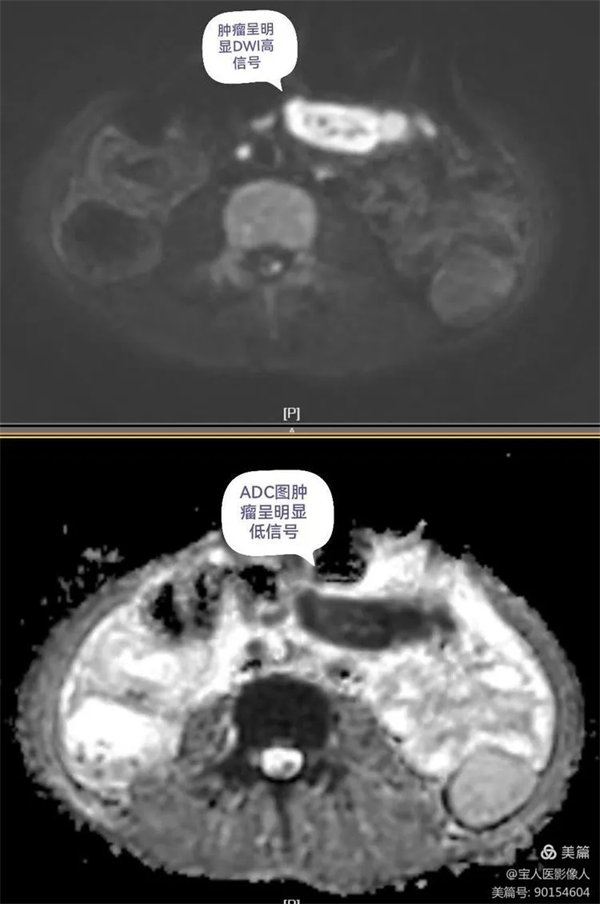

圖4:磁共振功能成像清晰顯示病變DWI呈明顯高信號,ADC圖呈低信號,腹膜后多發小結節灶。

圖5:DWI腫瘤呈明顯高信號,ADC圖呈低信號,中心為被包繞的腸系膜血管。